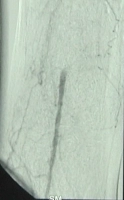

PM 311-3

Abb. 3: A. poplitea Abschnitt PI rechts füllt sich wieder

PM 311-4

Abb. 4: Teilverschlüsse der Unterschenkelarterien bds., Verschluss der A. poplitea Abschnitt PIII links